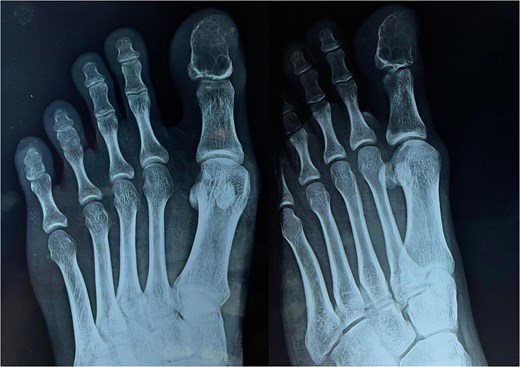

A 23-year-old boy with swelling over his left great toe for 8 months came to the surgery outpatient department of a tertiary care hospital. The enlargement began slowly and has now grown to measure approximately 2.5 × 1.5 × 1.5 cm (Fig. 1).

Left great toe presentation with normal skin and nails surrounding the growth.

The skin and nails surrounding the growth are normal. It was linked to pressure-related discomfort. There was no history of trauma in the past. There was no fever or presence of any other comorbidity. A systematic assessment revealed no anomalies. Tests for renal function, plasma glucose, complete blood count, and other standard laboratory procedures were all within normal ranges. A radiographic examination reveals a coarse trabeculation and an osteolytic lesion in the great toe’s distal phalanx, which may indicate a benign bone malignancy (Fig. 2).